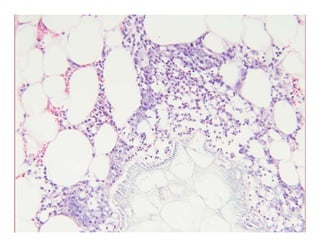

Subcutaneous fat necrosis of theSubcutaneous fat necrosis of the

bbnewbornnewborn

Normal epidermis and dermis with anNormal epidermis and dermis with anNormal epidermis and dermis with anNormal epidermis and dermis with an

underlying lobular panniculitisunderlying lobular panniculitis

–– Mixed inflammatory infiltrateMixed inflammatory infiltrateyy

Many fat cells retain their outlineMany fat cells retain their outline

–– Narrow clefts radiate from periphery of cellNarrow clefts radiate from periphery of cellNarrow clefts radiate from periphery of cellNarrow clefts radiate from periphery of cell

Contain doubly refractile needleContain doubly refractile needle--like crystalslike crystals

Same histology as Sclerema neonatorumSame histology as Sclerema neonatorum

–– Except, SN has less inflammationExcept, SN has less inflammation

Subcutaneous fat necrosisof theSubcutaneous fat necrosis of the bbnewbornnewborn Normal epidermis and dermis with anNormal epidermis and dermis with anNormal epidermis and dermis with anNormal epidermis and dermis with an underlying lobular panniculitisunderlying lobular panniculitis –– Mixed inflammatory infiltrateMixed inflammatory infiltrateyy Many fat cells retain their outlineMany fat cells retain their outline –– Narrow clefts radiate from periphery of cellNarrow clefts radiate from periphery of cellNarrow clefts radiate from periphery of cellNarrow clefts radiate from periphery of cell Contain doubly refractile needleContain doubly refractile needle--like crystalslike crystals Same histology as Sclerema neonatorumSame histology as Sclerema neonatorum –– Except, SN has less inflammationExcept, SN has less inflammation